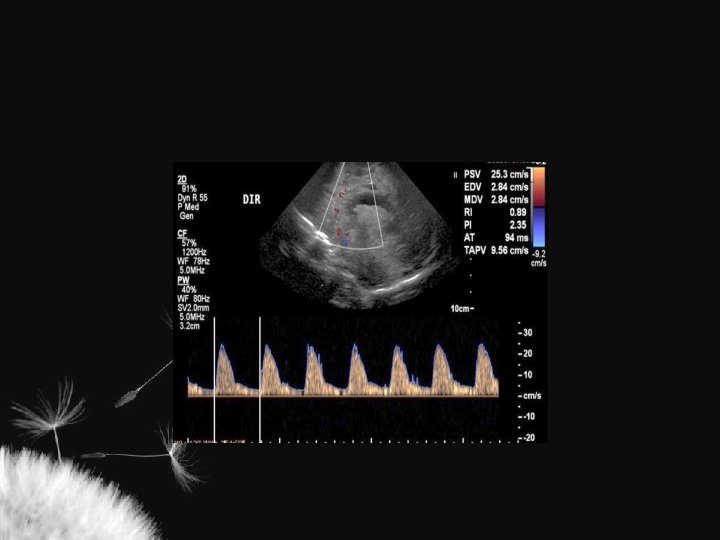

Considerações IR = S – D S Perfusão Q = A x TAV Aumento da PIC 1. Aumento da velocidade sistólica 2. Diminuição da velocidade diastólica Compressão fontanelar 1. Normal – aumenta até 6% 2. Diminuição da complacência craniana – > = 20%

LESÃO HIPÓXICO-ISQUÊMICA NO RN TERMO